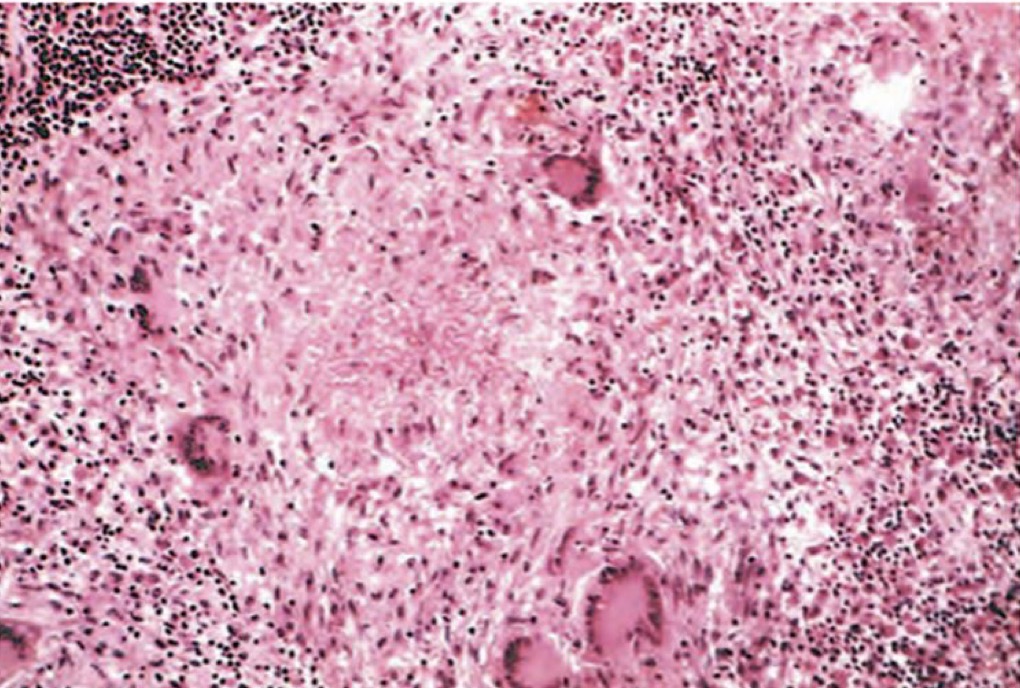

A- identify

B- Describe

A- Tuberculosis of lung

B- (A) large area of caseous necrosis contain yellow white cheesy debris ,(B) necrosis , at the upper right surrounded by granulomatous inflammatory cells